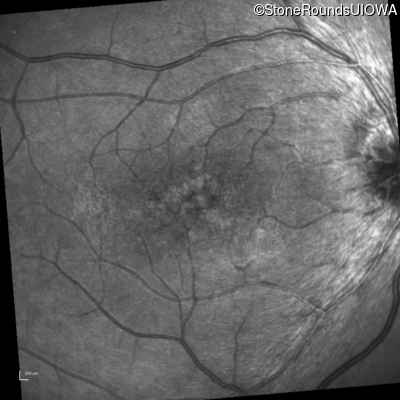

Infrared Fundus Photograph - Left - 20/50 -3

Exemplar